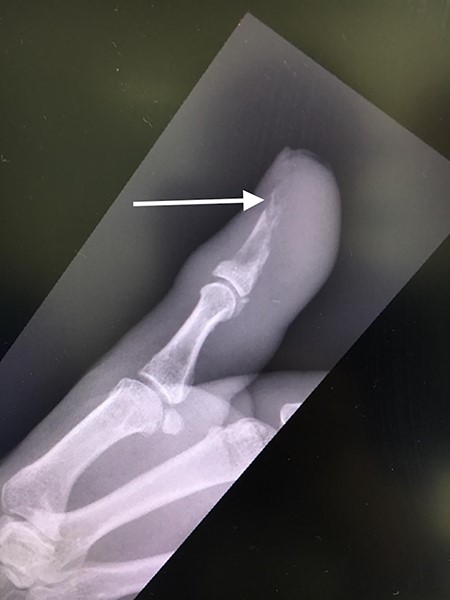

The patient was then reviewed 6 weeks after her initial presentation, following the results of the sarcoma MDT, which confirmed a benign tumour. At this point, the patient reported some tenderness around the surgical incision, but that her symptoms were improving. It was thought that she had no signs of ongoing infection in the thumb. The outcome was for monitoring of her symptoms with no indication for surgical excision. She had a follow-up X-ray in 6 weeks’ time that showed resolution of the lytic lesion (Figs 6 and 7).

AP follow-up radiograph of right thumb 6 weeks post-admission showing resolution of lytic lesion.

Lateral follow-up radiograph of right thumb 6 weeks post-admission showing resolution of lytic lesion.